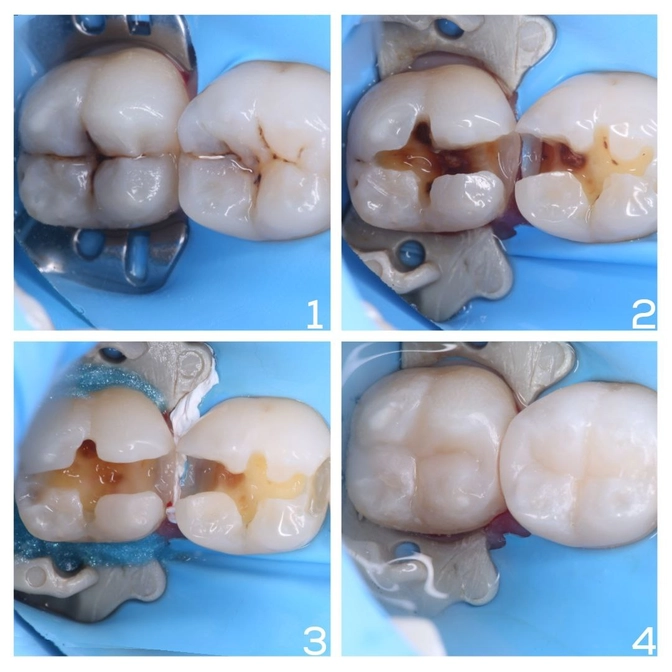

Шестой и седьмой зуб с глубоким рельефом.

Чернота — это всего лишь кариес.

Полости неглубокие, "нервы" удалять не пришлось.

✔️Пораженные ткани убрали;

✔️Отреставрировали зубы пломбировочным материалом;

✔️Восстановили анатомическую форму без углублений и борозд - пища и налет больше там застревать не будут.

✔️Зашлифовали и отполировали специальными резиночками и пастой.

✔️Эстетика и функциональность восстановлены идеально.